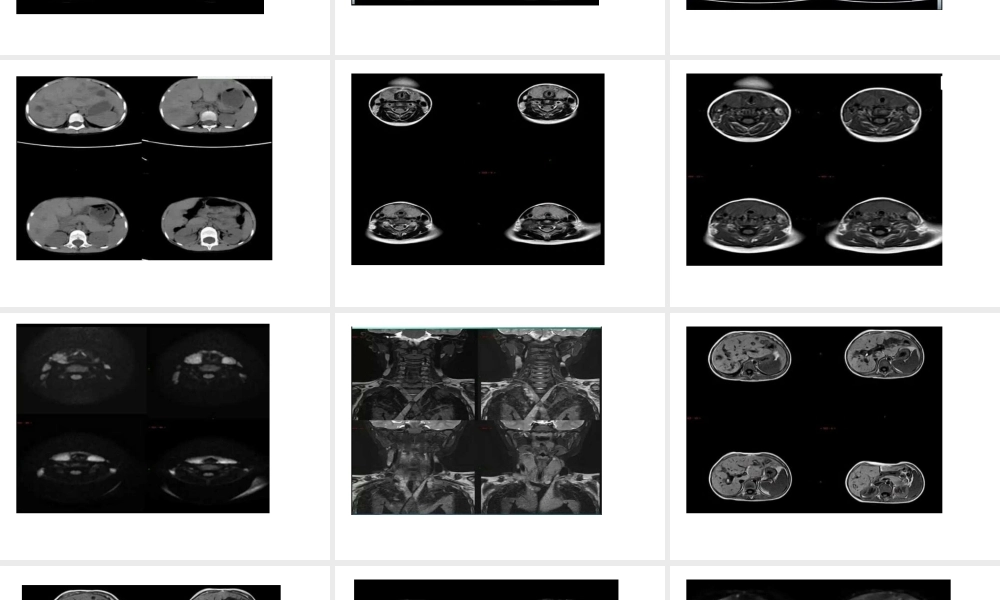

病例分析影像表现病理:颈淋巴结活检病理:朗格罕斯细胞组织细胞增生症小结:朗格罕斯细胞组织细胞增生症(LCH)是一种少见的原因不明的肉芽肿性疾病,发病率约为0.5/10万~1/10万,可以是单一器官或多系统多器官受累,骨骼最为常见,其次为皮肤、中枢神经系统、肝胆和脾脏,肺、淋巴结、软组织、骨髓、腺体及胃肠道等。本病可发生于任何年龄,但50%以上病例发生于1~15岁儿童,发病高峰为1~4岁,男女之比约2:1。【影像学表现】1.骨骼:颅骨、股骨、脊柱及肋骨为常见发病部位,①活动期:表现为类圆形圆形或不规则形单囊或多囊状溶骨性破坏,患骨轻度膨胀,皮质可碎裂,形成软组织肿块,此期在病理上以嗜酸性粒细胞及朗格罕氏组织细胞增生为主。②修复期:表现为骨破坏减少,增生增多,长骨骨干可增粗,密度增高。2.肺部:早期病变在CT上以结节状表现为主,晚期则以囊疱状表现为主,结节直径多小于10mm,结节多位于两肺上叶,下叶基底段少见,囊疱为薄壁或厚壁,少部分相邻囊疱融合成不规则形,结节可以向囊疱转变,囊疱间肺组织轻度磨玻璃样密度增高。3.肝脏:朗格罕斯细胞和炎性细胞浸润引起门静脉周围炎症和水肿,表现为带状或结节状低密度影,增强后可见强化;易于侵犯胆管,致硬化性胆管炎,导致胆管扩张。4.中枢神经系统:①占位性病变:垂体和下丘脑是LCH最早最常见的中枢神经系统部位,临床上以中枢性尿崩症为首发症状,在MR上表现为垂体柄增粗,增强呈渐进性均匀强化,但病变也始于脑内任何一个部位的血管外膜,并逐渐形成肉芽肿样肿块。②变性性病变:可发生于小脑齿状核、基底节区及脑干对称性炎性病变。5.其他:发生于腺体及淋巴结,主要表现为体积增大;发生于肌肉等软组织在MR上表现为T1等或低信号,T2为高信号,增强扫描有较明显强化。